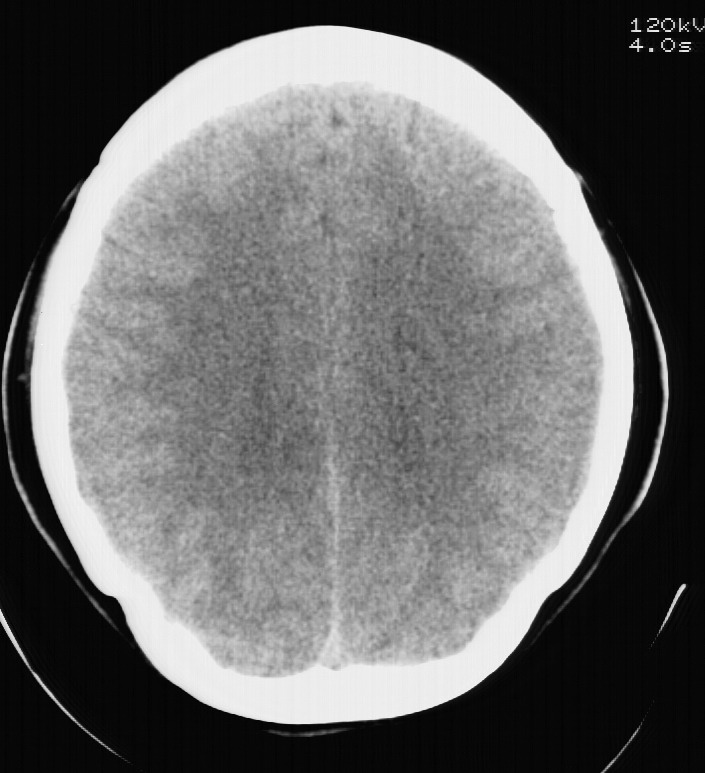

标题: CT5853:右额叶上部占位请会诊

女,34岁,自述头晕胀2年,近期感精神恍惚,无发热,实验室检查阴性。

水肿及强化不明显,考虑低分级胶质细胞瘤可能性大

水肿及强化都不明显!也没见钙化影!考虑i级星型细胞瘤可能性大!

右额叶低密度灶,脑回分离,无水肿及强化,考虑脑脓肿,建议mri检查